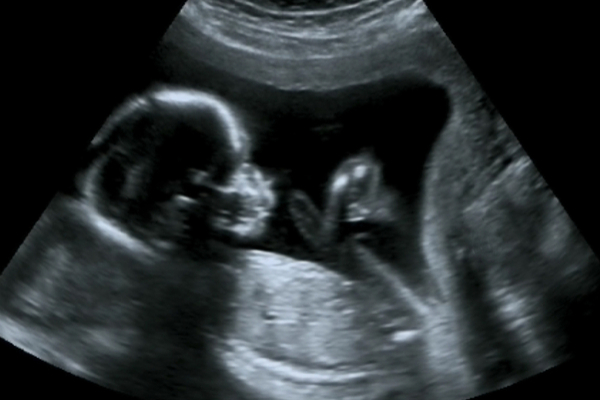

Riskli gebelikler; anneyi, bebeği veya her ikisini, hamilelik, doğum veya sonrasında tehdit edebilecek bazı problemlerin söz konusu olduğu gebeliklerdir. Tüm hamileliklerin yaklaşık %6’sını oluşturan riskli gebelikler, perinatoloji uzmanları tarafından takip edilir. Peki, riskli gebelik kriterleri nelerdir, hangi anne adaylarına riskli gebelik tanısı konur? Detaylar yazımızda…

Riskli Gebelik Nedir, Riskli Gebeliğin Kriterleri Nelerdir?

7)Çoğul Gebelikler

Bebek miktarı arttıkça gebeliğin riski de aynı paralelde artmaktadır. Çünkü anne adayı için artan fiziksel yük, anne adayının organlarının baskı altında kalması neticesinde zarar görebilmektedir. Aynı zamanda tek yumurta ikizleri birbirinden kan çalabilmekte ve bu durumda her iki bebeğin de hayatı risk altına girebilmektedir. Bu nedenle çoğul gebelikler de titizlikle takibi yapılması gereken riskli gebelik kategorisinde yer alır.

13)Bebekle İlgili Problemler

Bebeğin gelişimiyle ilgili problemler de riskli gebelik çatısı altındadır. Örneğin; bebekte anatomik bozukluklar, kromozomal bozukluklar, genetik sendromlar, kan hastalıkları veya enfeksiyon söz konusu ise gebelik riskli olarak değerlendirilir.

Perinatoloji Nedir?

Perinatoloji; kadın hastalıkları ve doğum uzmanlığı alanının riskli gebeliklerle ilgili olan bir yan dalıdır. Gebelik öncesi, gebelik, doğum ve doğum sonrasında anne ve bebeğin sağlığı için ortaya çıkabilecek sorunların nitelikli bir şekilde taranmasını, şüpheli durumlarda tanı ve tedavinin gerçekleştirilmesini sağlamaktadır. Gebelik öncesinde anne adayında kalp rahatsızlıkları, şeker hastalığı, karaciğer ve bağırsak rahatsızlıkları, enfeksiyonel hastalıklar, böbrek rahatsızlıkları vb. varsa, perinatolog ile görüşmesi önerilir.